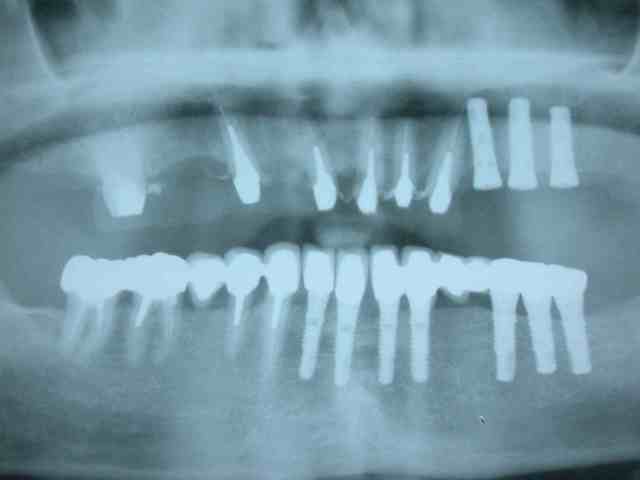

on évoluera par étapes :

1)mise en pace de 3 implants 35 36 37

2) on garde 34 pour stabiliser l'appareil

3)on attend l'ostéointégration des implants.

pano après